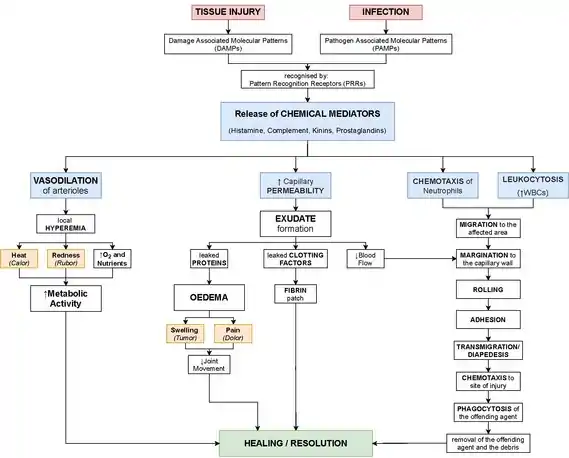

The process of acute inflammation is initiated by resident immune cells already present in the involved tissue, mainly resident macrophages, dendritic cells, histiocytes, Kupffer cells and mast cells. These cells possess surface receptors known as pattern recognition receptors (PRRs), which recognize (i.e., bind) two subclasses of molecules: pathogen-associated molecular patterns (PAMPs) and damage-associated molecular patterns (DAMPs). PAMPs are compounds that are associated with various pathogens, but which are distinguishable from host molecules. DAMPs are compounds that are associated with host-related injury and cell damage.

At the onset of an infection, burn, or other injuries, these cells undergo activation (one of the PRRs recognize a PAMP or DAMP) and release inflammatory mediators responsible for the clinical signs of inflammation. Vasodilation and its resulting increased blood flow causes the redness (rubor) and increased heat (calor). Increased permeability of the blood vessels results in an exudation (leakage) of plasma proteins and fluid into the tissue (edema), which manifests itself as swelling (tumor). Some of the released mediators such as bradykinin increase the sensitivity to pain (hyperalgesia, dolor). The mediator molecules also alter the blood vessels to permit the migration of leukocytes, mainly neutrophils and macrophages, to flow out of the blood vessels (extravasation) and into the tissue. The neutrophils migrate along a chemotactic gradient created by the local cells to reach the site of injury.[12] The loss of function (functio laesa) is probably the result of a neurological reflex in response to pain.

In addition to cell-derived mediators, several acellular biochemical cascade systems—consisting of preformed plasma proteins—act in parallel to initiate and propagate the inflammatory response. These include the complement system activated by bacteria and the coagulation and fibrinolysis systems activated by necrosis (e.g., burn, trauma).[12]

Vasodilation and increased permeability

As defined, acute inflammation is an immunovascular response to inflammatory stimuli, which can include infection or trauma.[20][21] This means acute inflammation can be broadly divided into a vascular phase that occurs first, followed by a cellular phase involving immune cells (more specifically myeloid granulocytes in the acute setting).[20] The vascular component of acute inflammation involves the movement of plasma fluid, containing important proteins such as fibrin and immunoglobulins (antibodies), into inflamed tissue.

Upon contact with PAMPs, tissue macrophages and mastocytes release vasoactive amines such as histamine and serotonin, as well as eicosanoids such as prostaglandin E2 and leukotriene B4 to remodel the local vasculature.[22] Macrophages and endothelial cells release nitric oxide.[23] These mediators vasodilate and permeabilize the blood vessels, which results in the net distribution of blood plasma from the vessel into the tissue space. The increased collection of fluid into the tissue causes it to swell (edema).[22] This exuded tissue fluid contains various antimicrobial mediators from the plasma such as complement, lysozyme, antibodies, which can immediately deal damage to microbes, and opsonise the microbes in preparation for the cellular phase. If the inflammatory stimulus is a lacerating wound, exuded platelets, coagulants, plasmin and kinins can clot the wounded area using vitamin K-dependent mechanisms[24] and provide haemostasis in the first instance. These clotting mediators also provide a structural staging framework at the inflammatory tissue site in the form of a fibrin lattice – as would construction scaffolding at a construction site – for the purpose of aiding phagocytic debridement and wound repair later on. Some of the exuded tissue fluid is also funneled by lymphatics to the regional lymph nodes, flushing bacteria along to start the recognition and attack phase of the adaptive immune system.

Acute inflammation is characterized by marked vascular changes, including vasodilation, increased permeability and increased blood flow, which are induced by the actions of various inflammatory mediators.[22] Vasodilation occurs first at the arteriole level, progressing to the capillary level, and brings about a net increase in the amount of blood present, causing the redness and heat of inflammation. Increased permeability of the vessels results in the movement of plasma into the tissues, with resultant stasis due to the increase in the concentration of the cells within blood – a condition characterized by enlarged vessels packed with cells. Stasis allows leukocytes to marginate (move) along the endothelium, a process critical to their recruitment into the tissues. Normal flowing blood prevents this, as the shearing force along the periphery of the vessels moves cells in the blood into the middle of the vessel.

Cellular component

Leukocyte extravasation

Various leukocytes, particularly neutrophils, are critically involved in the initiation and maintenance of inflammation. These cells must be able to move to the site of injury from their usual location in the blood, therefore mechanisms exist to recruit and direct leukocytes to the appropriate place. The process of leukocyte movement from the blood to the tissues through the blood vessels is known as extravasation and can be broadly divided up into a number of steps: